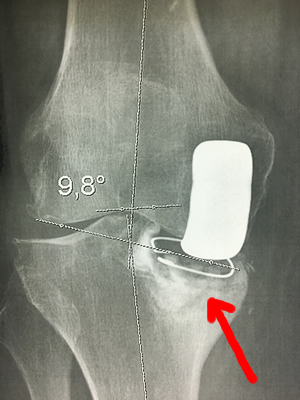

Exemple de reprise de prothèse

Ci-dessous, vous pouvez voir la radio d'une prothèse partielle interne, 12 ans après la pose initiale, avec enfoncement de la pièce tibiale dans le tibia (flèche rouge) et la radio de la prothèse de reprise avec une longue tige.